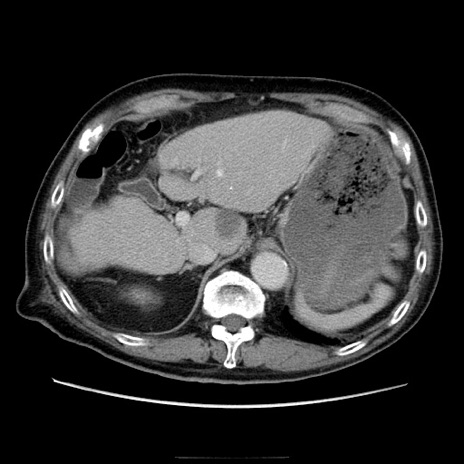

症例21(横断像)

【症例】70歳代男性

【主訴】腹痛

【現病歴】肝硬変・肝細胞癌にてかかりつけの方。約9時間前に食後より腹痛出現。症状が徐々に増悪し、嘔吐出現したため来院。

【既往歴】肝硬変、肝細胞癌(RFA、TACE後)

【身体所見】意識清明、表情苦悶様、BT 36℃、BP 129/78mmHg、P 88bpm、SpO2 97%(RA)、右上腹部から心窩部にかけて圧痛あり、反跳痛なし、筋性防御あり。

【データ】WBC 5800、CRP 0.16